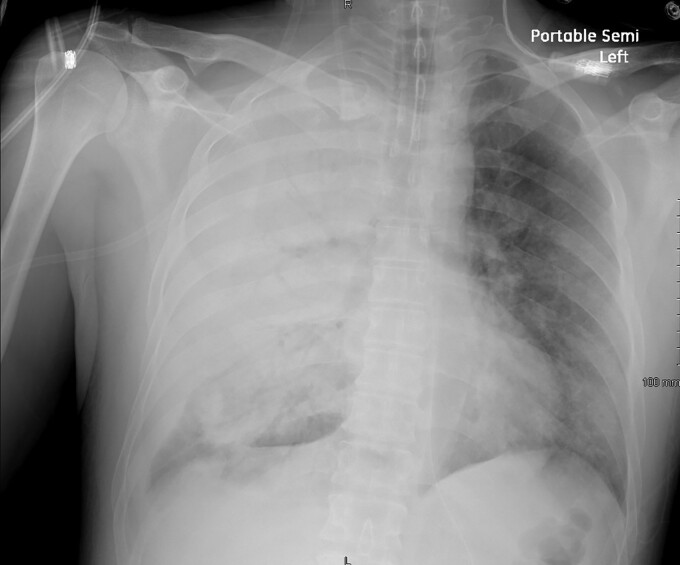

People diagnosed with welder's anthrax had abnormal chest imaging, including pneumonia and pleural effusions. Clinicians should suspect welder's anthrax if a welder or metalworker has a severe, rapidly progressive pneumonia. Mediastinitis, which is usually seen in anthrax, is not typical in welder's anthrax.